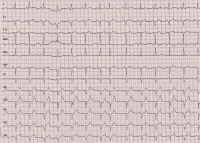

Die akute ischämische Mitralklappeninsuffizienz - ein kardiologischer Notfall: Fallpräsentation einer 79-jährigen Patientin mit Koronarsyndrom// Acute ischaemic mitral regurgitation – an emergency

Journal für Kardiologie - Austrian Journal of Cardiology 2016; 23 (3-4): 80-86 Volltext (PDF) Fallbeschreibung Fragen zum Artikel Abbildungen mit Filmsequenzen